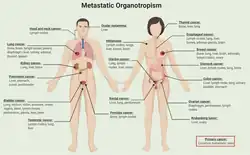

Les organes les plus fréquemment concernés par le développement de métastases sont toujours les mêmes, certaines tumeurs tendant à essaimer dans des organes particuliers, comme l'a suggéré il y a plus d’un siècle, en 1889, la « théorie de la graine et du sol » due à Stéphane Paget.

Le cancer de la prostate, par exemple, métastase généralement dans les os. De la même façon, le cancer du côlon tend à métastaser dans le foie. Chez les femmes, le cancer de l'estomac métastase souvent dans les ovaires, où il forme une tumeur de Krukenberg. On avait remarqué que le plus souvent les principaux organes-cibles des métastases sont ceux qui jouent un rôle de filtre dans le corps sain (ex. : foie) ou dans le système immunitaire (ex. : glandes surrénales).

- Le foie accueille le plus de métastases d'adénocarcinomes, même quand ces derniers se développent dans l'enfance. On pensait que c'était surtout parce qu'il filtre la circulation digestive, en provenance de la veine porte, mais une étude[4] publiée en 2010 laisse penser que le système immunitaire pourrait en être la raison principale ; cette étude a utilisé des souris mutantes comme modèle animal. Une souche mutante développait spontanément un cancer du pancréas, une autre présentait un cancer avancé du côlon, se propageant à l'abdomen. Les chercheurs ont observé dans le foie — dès les premiers stades de développement du cancer — une expansion de deux types de cellules immunitaires myeloïdes suppressives dans le foie présentant des phénotypes (CD11b+ Gr1+) et caractéristiques fonctionnelles différentes. Ces cellules deviennent alors les leucocytes hépatiques dominants, concomitamment aux phénomènes de cancérisation du foie. Lutter contre ces cellules immunitaires de suppression (tueuses de lymphocytes T) dans le foie lors du développement d'un cancer pourrait empêcher la propagation du cancer au foie[4].

- Après le foie, ce sont les poumons qui sont le plus touchés (ils voient passer toute la circulation du corps).

- Mais les os, le cerveau, et bien que moins souvent, la plupart des autres organes peuvent également être touchés.

En plus de leur rôle dans l’amorçage de la niche pré-métastatique, les exosomes participent à l’organotropisme des cellules cancéreuses. Cette affinité envers certains organes provient de l'avidité exosomale pour des cellules hôtes spécifiques[48]. L'étude de l'expression protéomique exosomale du cancer des os a montré différents modèles d'intégrines, dans lesquels les intégrines exosomales α6β4 et α6β1 étaient corrélées aux métastases pulmonaires, tandis que l'intégrine exosomale αvβ5 était associée aux métastases hépatiques[49]. L'absorption des intégrines dans le site secondaire a conduit à la phosphorylation de la protéine oncogène Src et à l'expression du gène pro-inflammatoire S100 [49]. Le ciblage de ces intégrines a diminué l'absorption exosomale et diminue le nombre de métastases pulmonaires et hépatiques par diminution de l’absorption des exosomes[49]. Les autres protéines et lipides membranaires associés à la matrice extra-cellulaire influencent le ciblage spécifique des exosomes sur leurs cellules hôtes spécifiques[49],[50],[51],[52],[53]. De plus, l'internalisation exosomale par les cellules hôtes cibles active des voies endocytaires hétérogènes telles que la clathrine, le radeau lipidique et l'absorption médiée par la cavéoline[54],[55].

L'organotropisme a été abordé pour la première fois par Paget dans le cadre de l'hypothèse des « graines et du sol »[116]. La recherche sur le cancer du sein a soutenu cette hypothèse[117],[118], les chercheurs élucidant les bases génétiques de la colonisation du cancer dans des organes distants[119]. De plus, le microenvironnement de l'hôte joue un rôle dans l’extravasation et la colonisation des cellules cancéreuses à des sites spécifiques.Par exemple, dans le cancer du sein, Le flux de calcium, par exemple, a été identifié comme un mécanisme interactif entre la niche ostéogénique et les cellules tumrales , qui favorise la progression des métastases osseuses[120].